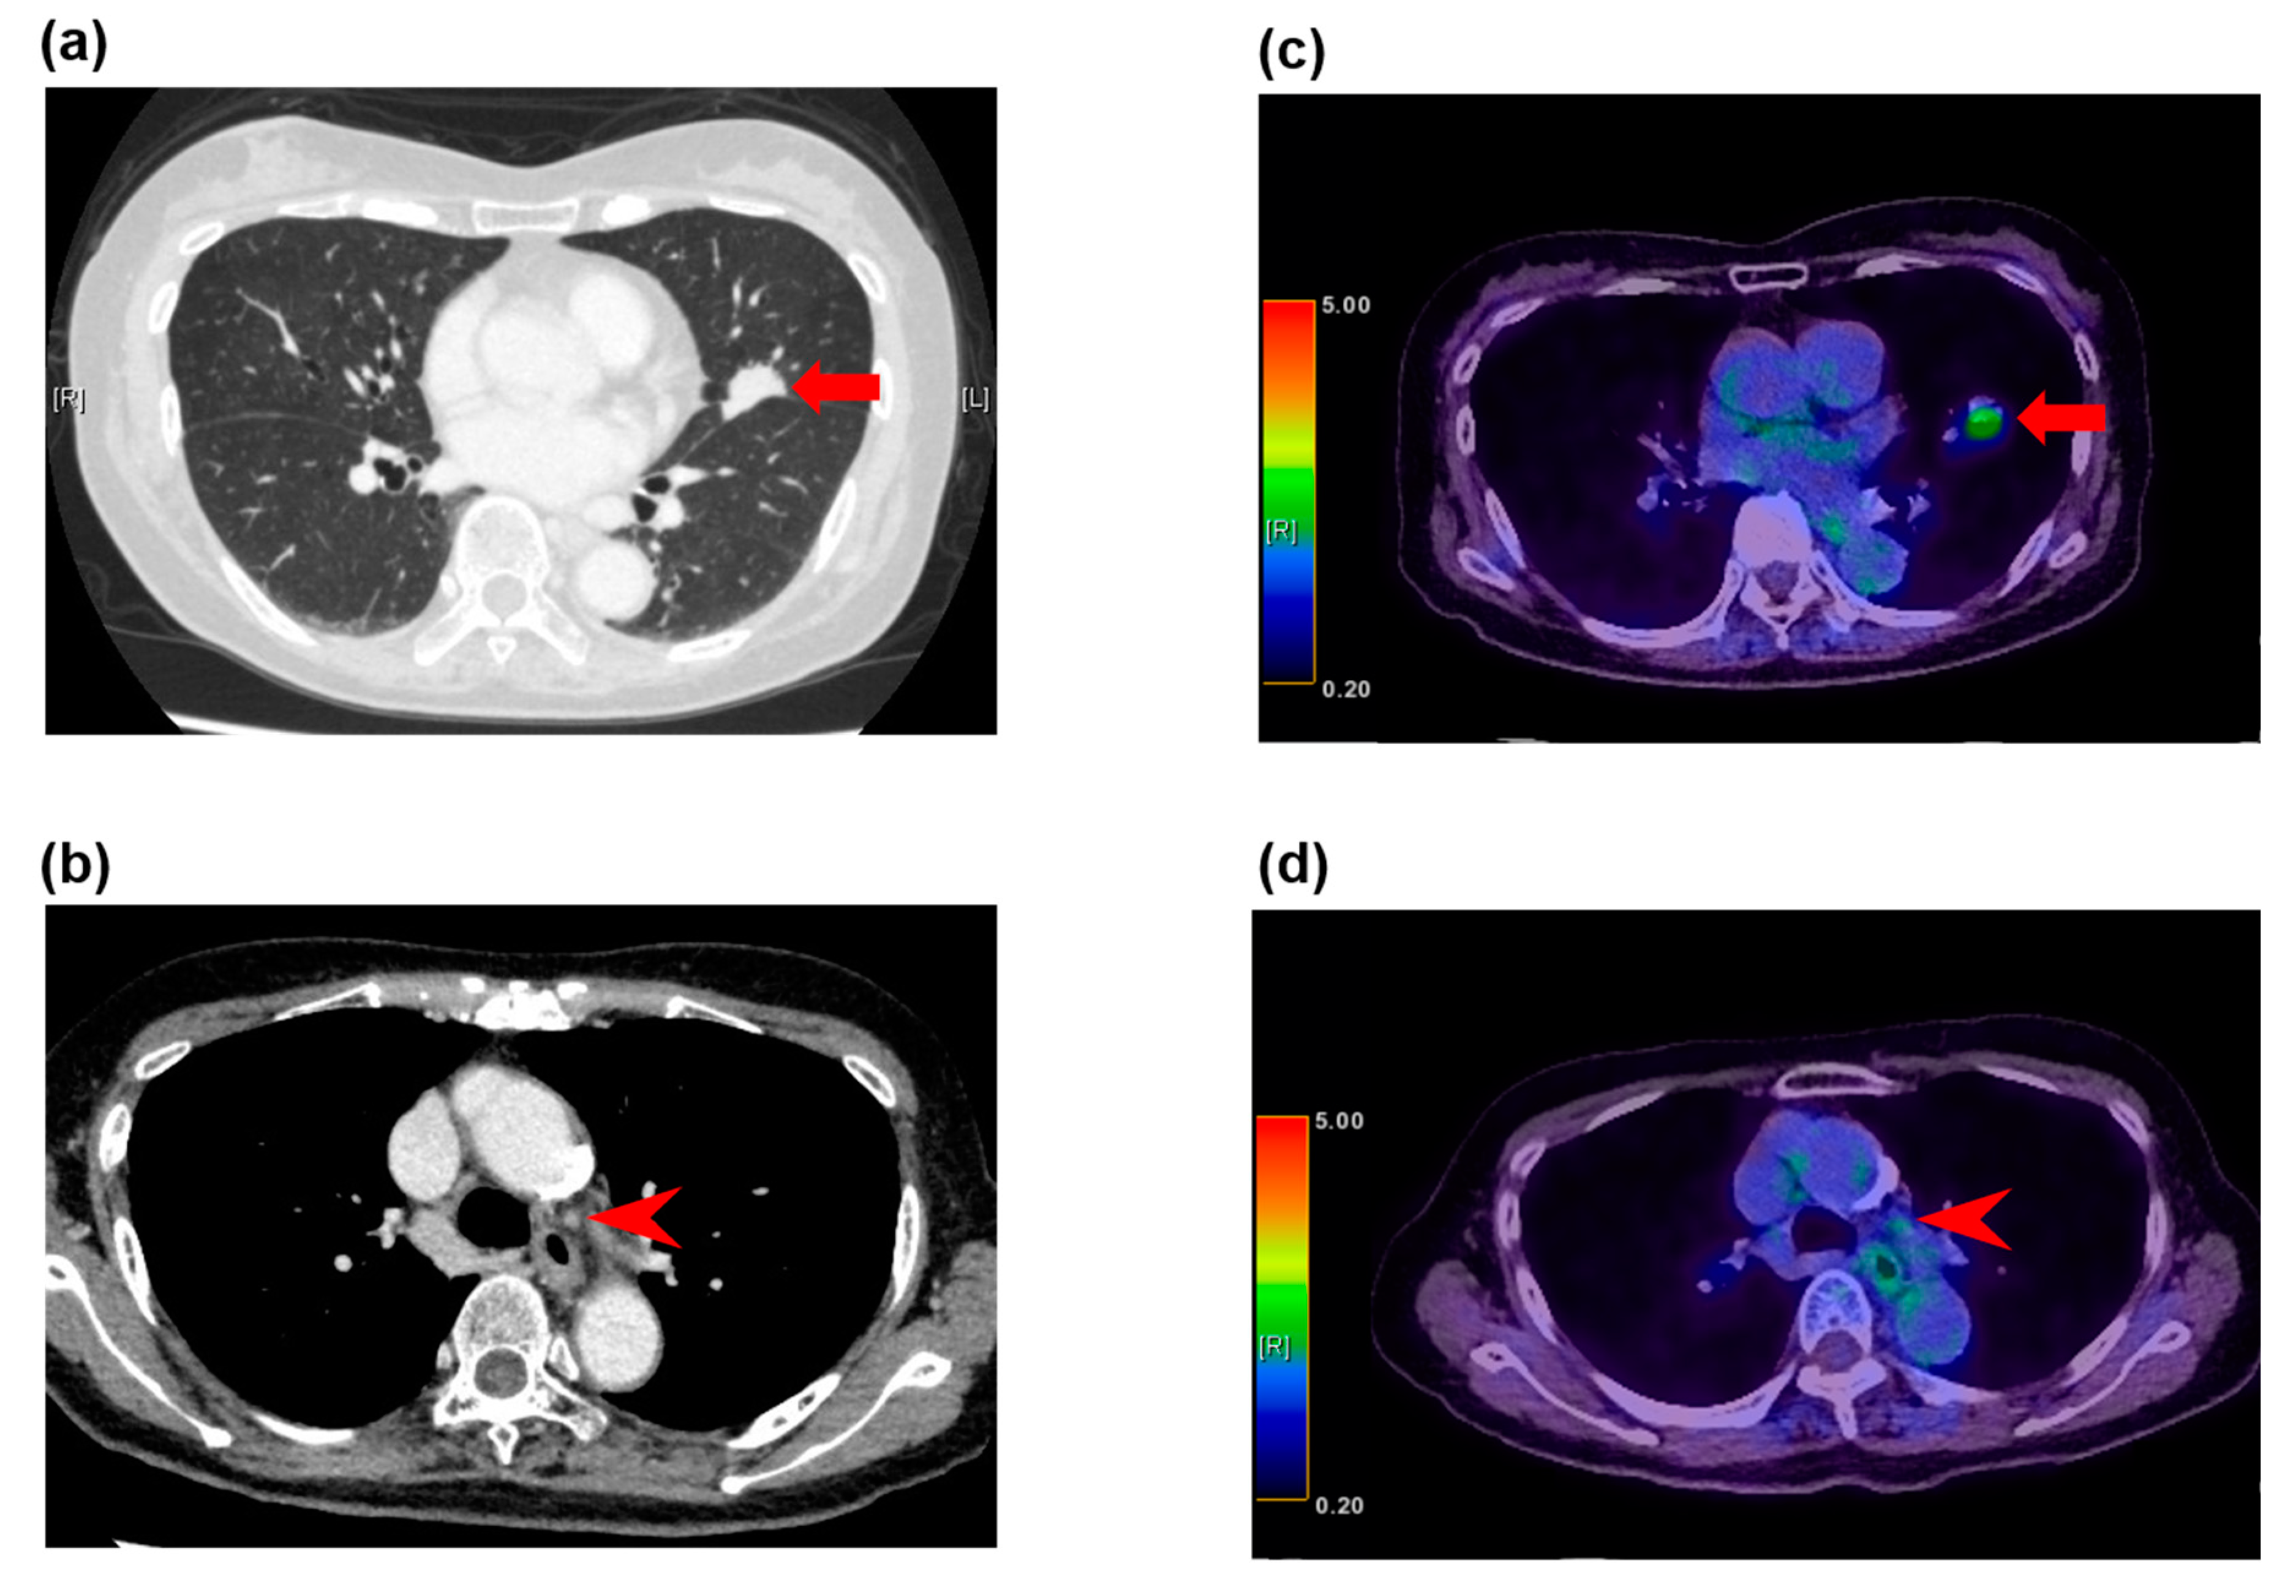

Figure 1.

False negative fluorodeoxyglucose F 18 positron emission tomography (FDG-PET) findings in normal-sized lymph nodes in a 79-year-old woman with adenocarcinoma. (a) The computed tomography (CT) image shows a left upper lobe tumor (arrow), (b) and nonenlarged station 5 lymph nodes (arrowhead). (c) The FDG-PET/CT image shows FDG accumulation with a maximum standardized uptake value (SUV) of 3.3 (arrow) in the adenocarcinoma in the left upper lobe, (d) and no FDG accumulation in the normal-sized station 5 lymph nodes (arrowhead). These lymph nodes demonstrated metastatic disease at histopathologic examination of the specimen from surgical biopsy.